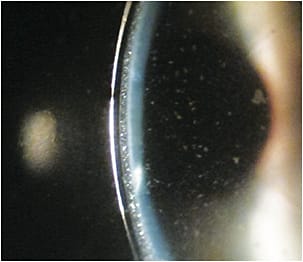

Midday fogging (MDF) occurs when particulates accumulate within the reservoir (Pucker and Laurent, 2018) (Figure 1). This affects 20% to 30% of scleral lens patients (Walker et al, 2016). In a recent Contact Lenses Today poll, MDF was cited by 44% of respondents as the most frequent scleral lens complication that they encounter in practice (Nichols, 2018).

Although MDF has not been shown to negatively affect the anterior ocular surface, it can result in loss of clarity and the need to refresh the lens during the course of daily wear (Carracedo et al, 2017).